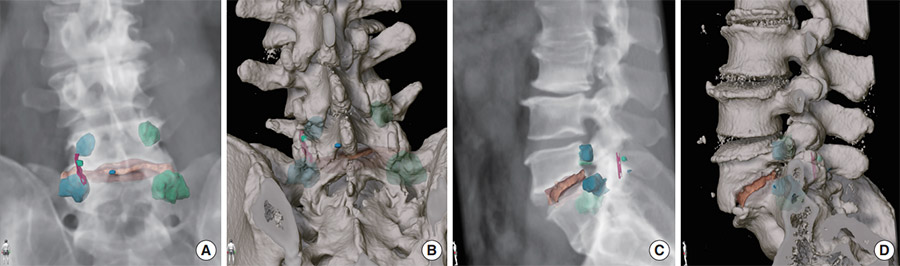

Landmarks for a L5/S1 transforaminal lumbar interbody fusion via left sided surgical approach highlighted on a CT 3D reconstruction posterior view (A, B) and left sided lateral view (C, D). (Credit: Neurospine, September 2022)

In the images above, L5 inferior medial edge of the lamina is indicated in blue; L5 pars, green; L5/S1 superficial facet joint space, purple; S1 “pedicle” ipsilateral, light blue; L5 pedicle ipsilateral, light blue; L5/S1 posterior part disc space, orange; and L5 and S1 pedicle contralateral, light green.